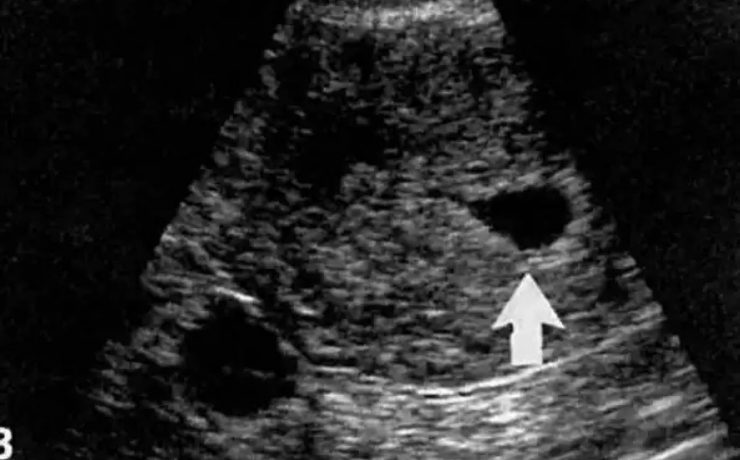

En este estudio se analiza la utilidad del ultrasonido en el estudio de la paciente estéril, específicamente con ultrasonido con aplicación de doppler, de Power doppler y la ecografía 3D para analizar los cambios cualitativos y cuantitativos que se observan en la irrigación del ovario en pacientes estériles, en pacientes